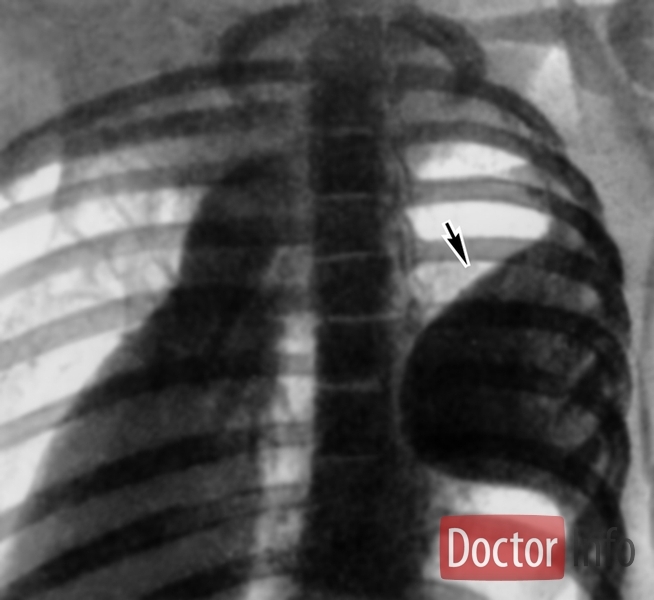

Может стать первым проявлением туберкулеза легких, Микобактерия туберкулеза может поразить отделы легких, расположенные наиболее поверхностно, рядом с плеврой (оболочка, покрывающая плевру), в таких случаях сначала проявляются признаки плеврита, так как микобактерия поражает и плевру. Развивается воспаление с постепенным разрушением плевры рядом с очагом в легких.